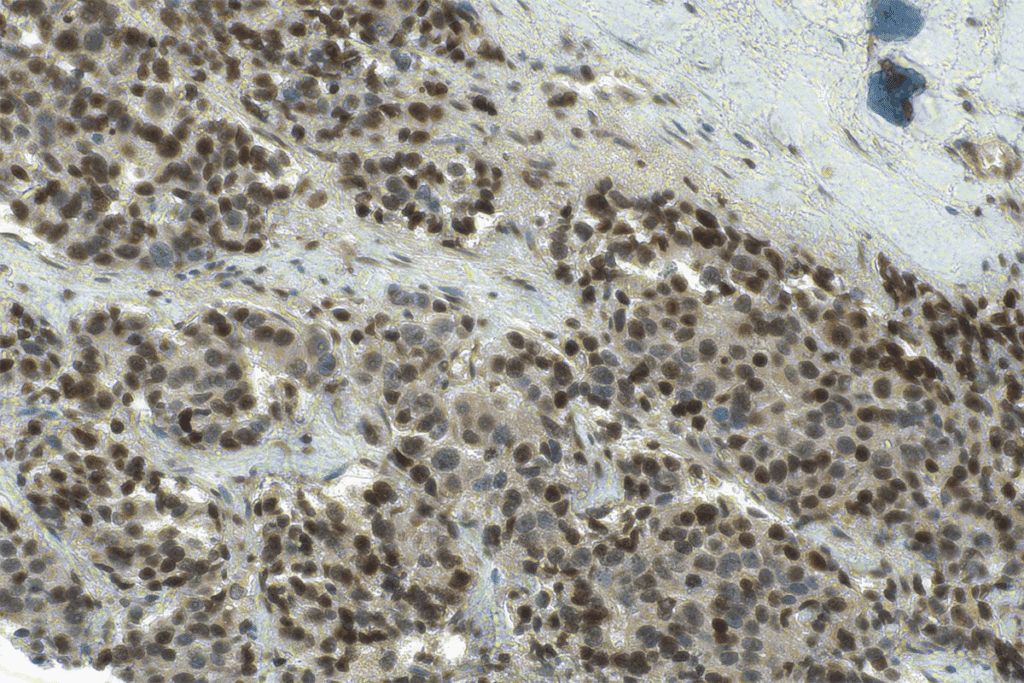

Microscopic Appearance

Under a microscope, CIS cells show distinct features. Their structure is disorganized, unlike normal cells. This disorganization is a sign of abnormal growth in CIS.

| CIS Cells | Disorganized | Present | No Stromal Invasion |

CIS is classified as stage 0 cancer (TisN0M0). Knowing about CIS’s biology is key for early detection and treatment.